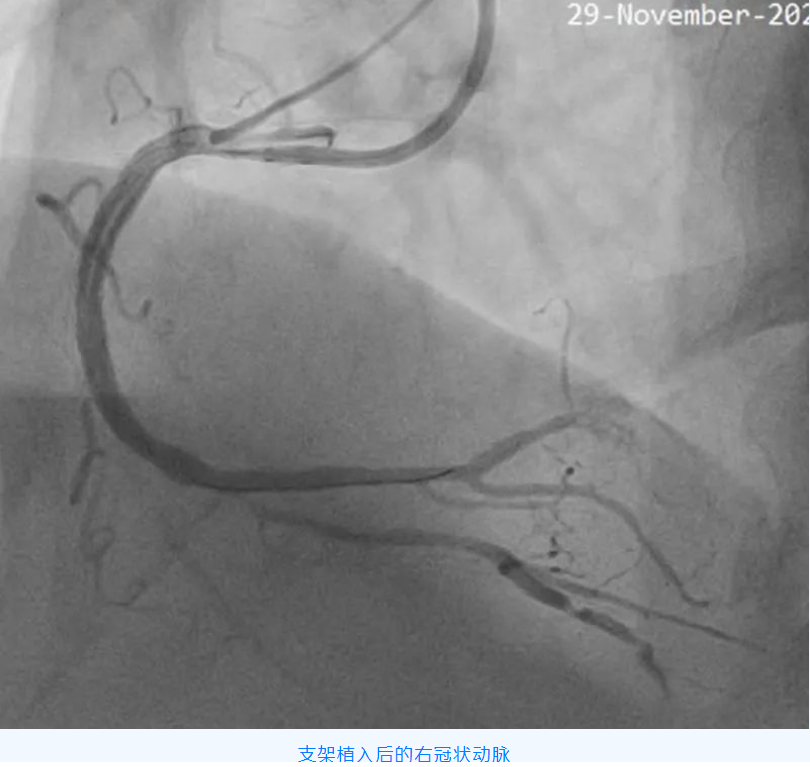

该例CTO 的成功开通,标志着星城院区心血管内科诊疗水平又有了新的突破。

家住阎村的赵爷爷,今年75岁,近一年来反复出现胸痛、胸闷,行冠脉CTA检查发现冠状动脉三支病变,其中一根血管完全闭塞,需进一步行冠脉介入治疗。

冠状动脉慢性完全闭塞病变(CTO),即冠状动脉血管腔完全闭塞,且持续闭塞的时间大于 3 个月的病变。对于病人而言,成功开通 CTO 可以延长生命、改善心脏功能、增加心肌电活动稳定性,减少心律失常事件,而且还可以增加以后可能出现的冠状动脉闭塞事件耐受性及提高生活质量,越是年轻患者,开通 CTO 获益越大。